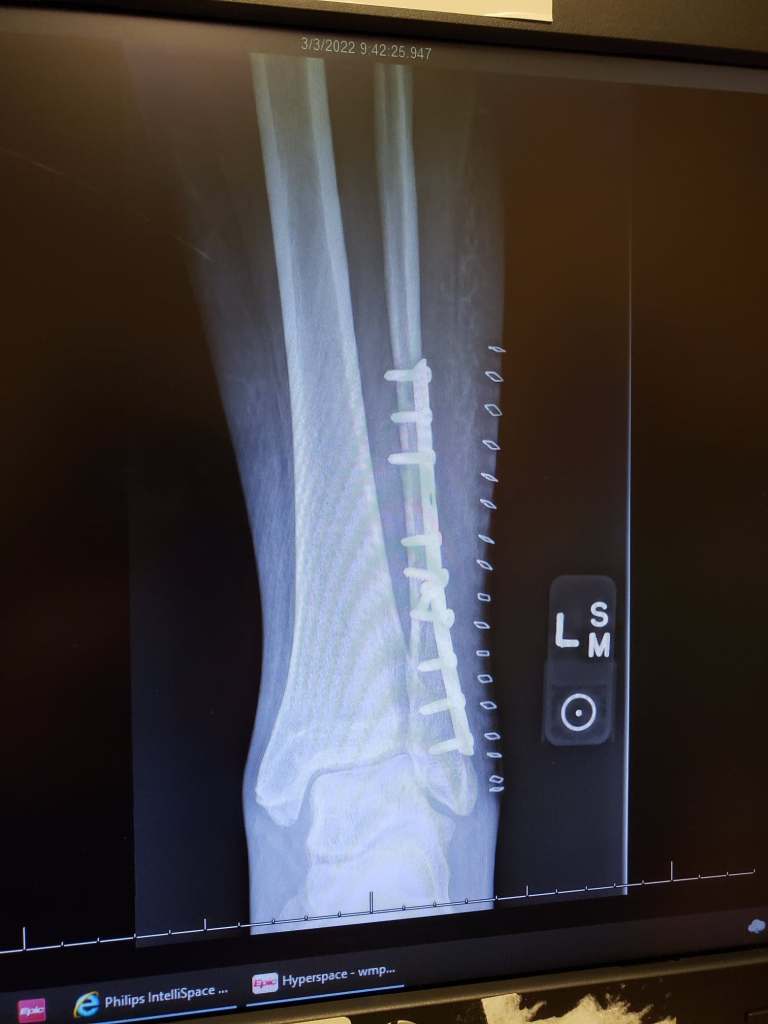

Tried to write an update on my fracture, three-and-a-half weeks out. Actually, I did write and post an update earlier today, nearly an hour ago. I spent a good bit of time writing and selecting pictures.